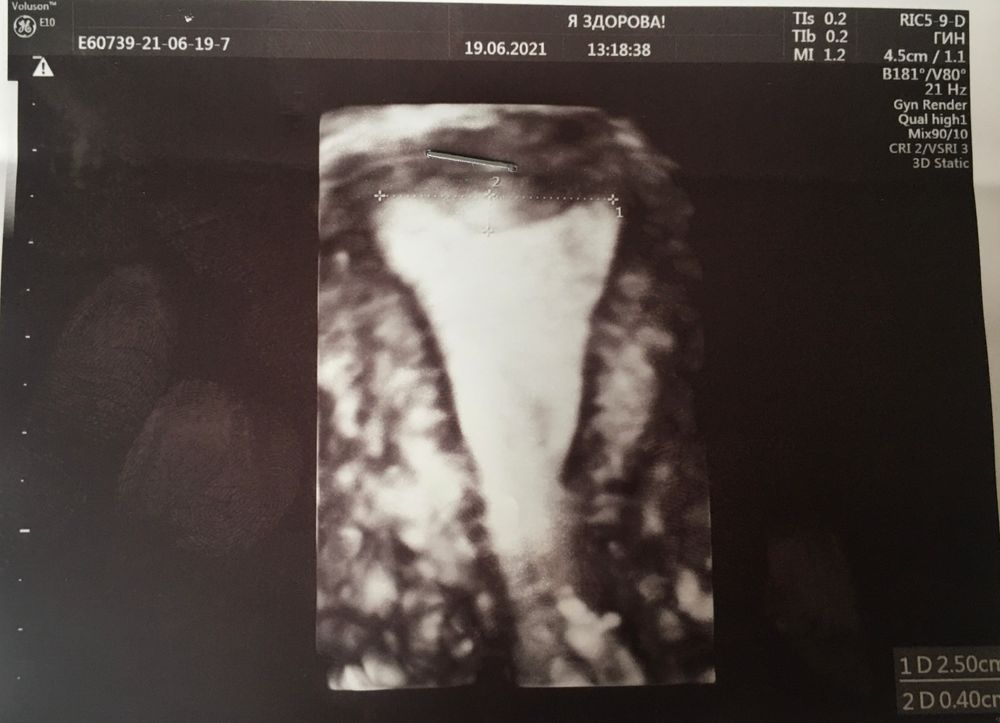

Я: почему вы написали в своём письме, что причина того, что не удалось полностью удалить остатки плодного яйца, является форма моей матки. Седловидная. Вы ведь видите, что доктор, а я у неё наблюдаюсь с октября 2021 года, ни разу не ставила данный диагноз в протоколах приёма. Она делала гистеру перед переносом. Все мои предыдущие узи, сделанные у других специалистов, могу показать, говорят о том, что у меня обычная форма матки. Да вот тут тоже гляньте Пятых, Каплина ставит «форма матки: обычная»! (Показываю узи матки, где запечатлена вся форма матки). Это по вашему седловидная?